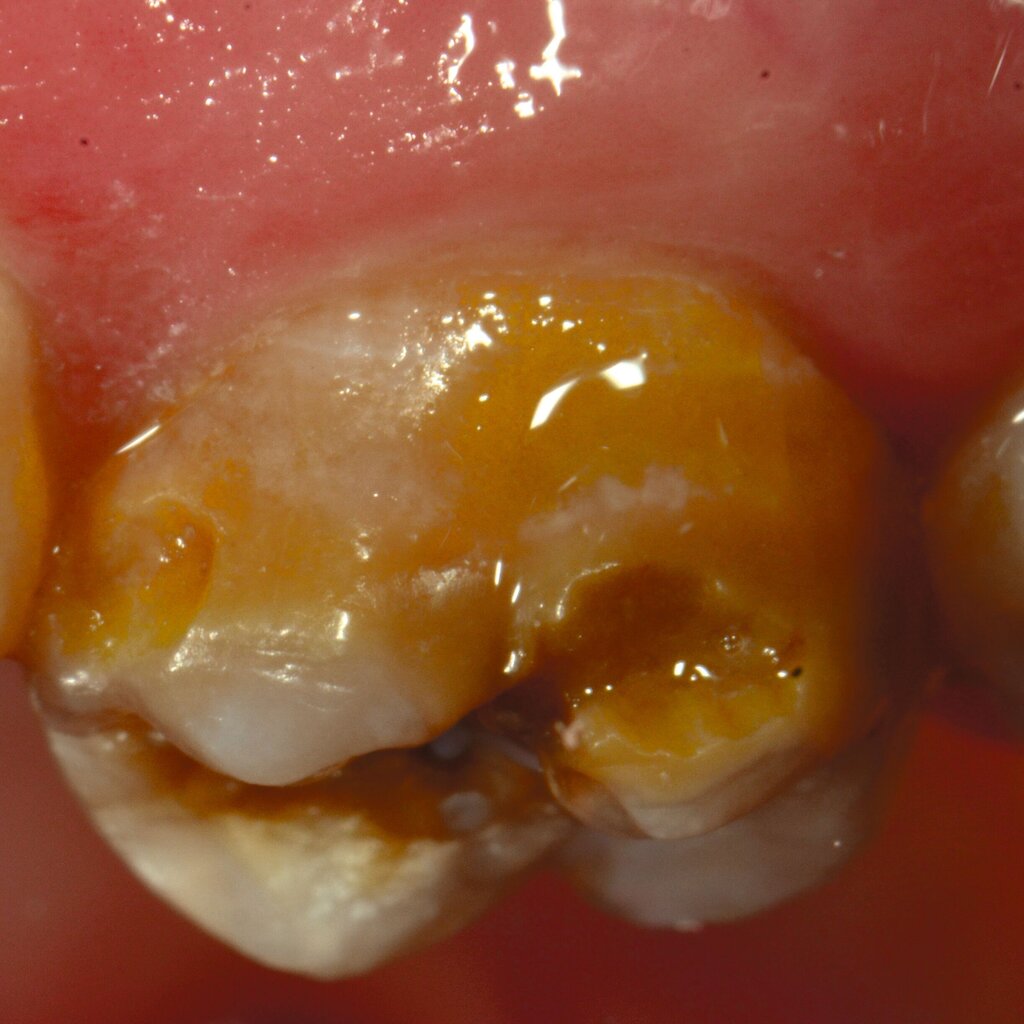

An umfangreich hypomineralisierten Zähnen können Schmelzeinbrüche (engl.: „enamel breakdown“ oder „enamel desintegration“, Abbildung 5) auftreten [Lygidakis et al., 2010; 2022]. Da diese oftmals die Folge einer fehlenden Belastungsfähigkeit des Zahnschmelzes sind und erst nach der Einstellung der Zähne in die Okklusion auftreten, werden sie auch als posteruptive Schmelzeinbrüche bezeichnet. Sie sind häufig im Bereich der Kauflächen beziehungsweise Höcker der Molaren zu finden, führen zur Dentinexposition und damit einhergehend zu ausgeprägten Hypersensitiven insbesondere bei Kindern, deren Zähne gerade erst durchgebrochen sind [Linner et al., 2021].

Bei post- beziehungsweise präeruptiven Oberflächendefekten ergibt sich in einigen Fällen die Indikation zur Restauration dieser MIH-Zähne. Unter Verweis auf die Lokalisation von MIH-bedingten Hypomineralisationen außerhalb der typischen Kariesprädilektionsstellen – zum Beispiel okklusale Fissuren und Grübchen oder Approximalflächen – werden diese als „atypische Restaurationen“ (engl.: „atypical restoration“, Abbildung 6) klassifiziert. Als ein weiteres Erkennungsmerkmal gilt die Präsenz von Hypomineralisationen im Bereich der Restaurationsränder. MIH- und kariesbedingte Restaurationen können und sollten sicher voneinander abgegrenzt werden.

Für die Dokumentation und Klassifikation der MIH wurden verschiedene Systeme vorgeschlagen. Als historisch und veraltet gilt der (modifizierte) DDE-Index. Demgegenüber haben die Kriterien der EAPD – abgegrenzte Opazitäten (Abbildung 3 und 4), Schmelzeinbrüche (Abbildung 5), atypische Restaurationen (Abbildung 6) – mittlerweile die weiteste Verbreitung gefunden. Diese wurden 2003 erstmals zur Beschreibung der MIH auf empirischer Basis publiziert [Weerheijm et al., 2003] und den Jahren 2010 und 2022 im Rahmen der damaligen MIH-Workshops bestätigt [Lygidakis et al., 2010; 2022].